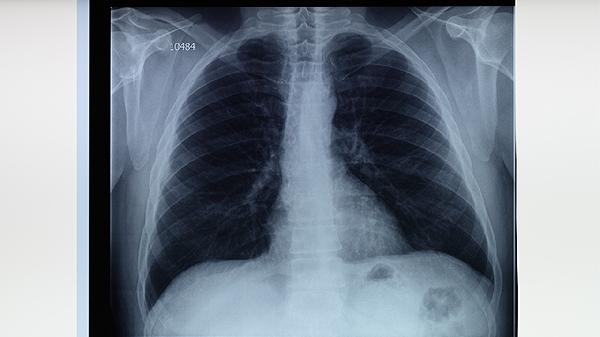

肺结核患者用药期间应保持高蛋白饮食如鸡蛋、鱼肉,补充维生素B族和维生素C。避免饮酒及高脂饮食加重肝脏负担,适当进行散步等低强度运动增强体质。出现持续头晕、皮肤黄染或血尿等严重副作用时,须立即停药并急诊处理。治疗全程需配合胸部CT复查评估疗效,耐药结核患者可能需调整为期18-24个月的个体化方案。